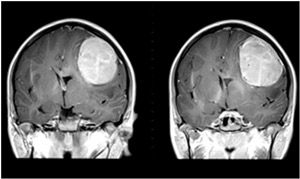

Finally, Wang’s group tested the therapeutic effect of the constructs in live animals. They grafted modified, human glioblastoma cells expressing luciferase into the brains of mice, and then injected the constructs into these sites. Confirming the cell culture results, the constructs suppressed luciferase expression and eradicated the tumors upon addition of ganciclovir; healthy cells were unaffected. In mice given salt water instead of ganciclovir, however, the tumors continued to grow.